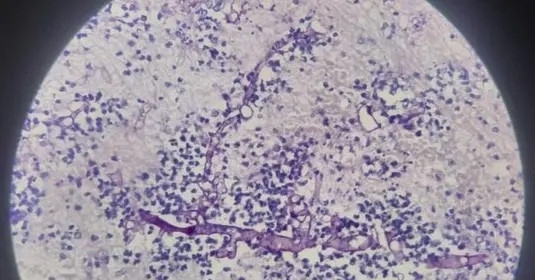

Trước diễn biến nguy kịch, người bệnh được chỉ định phẫu thuật cấp cứu lấy khối máu tụ não. Mẫu bệnh phẩm được gửi làm xét nghiệm giải phẫu bệnh. Kết quả cho thấy hoại tử mô não lan rộng, kèm theo nhiều sợi nấm kích thước lớn. Các bác sĩ chẩn đoán áp xe não do nhiễm nấm xâm lấn, hướng đến nấm đen.

Sau phẫu thuật, người bệnh được chuyển đến Bệnh viện Bệnh Nhiệt đới Trung ương (Hà Nội) để tiếp tục điều trị chuyên sâu. Xét nghiệm PCR sau đó xác định người bệnh nhiễm nấm thuộc bộ Mucorales, qua đó khẳng định chẩn đoán nấm đen xâm lấn hệ thần kinh trung ương.